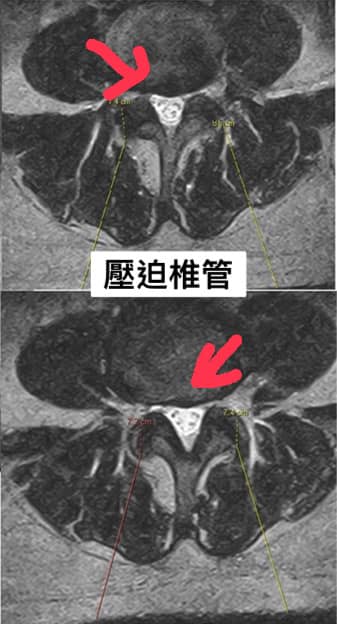

1.L4 on L5 gradeⅠ 腰椎弓解離

2.椎管狹窄

❇️脊椎整合中醫微創原理:當脊椎體向前滑脫時,附近的神經會被夾住或刺激到,除此之外,脊管變小也會造成神經的刺激和壓迫,為了解決這個問題,把神經根附近卡壓軟組織鬆開,神經壓力才能釋放